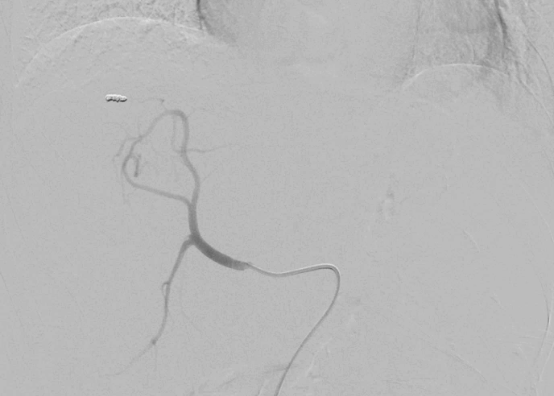

RH catheter 사용

3cc/sec, total 15cc